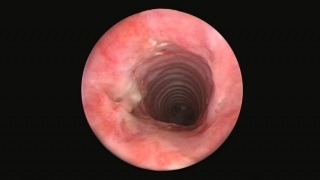

- Endoscopic view of tracheal stenosis after treatment with balloon dilation.